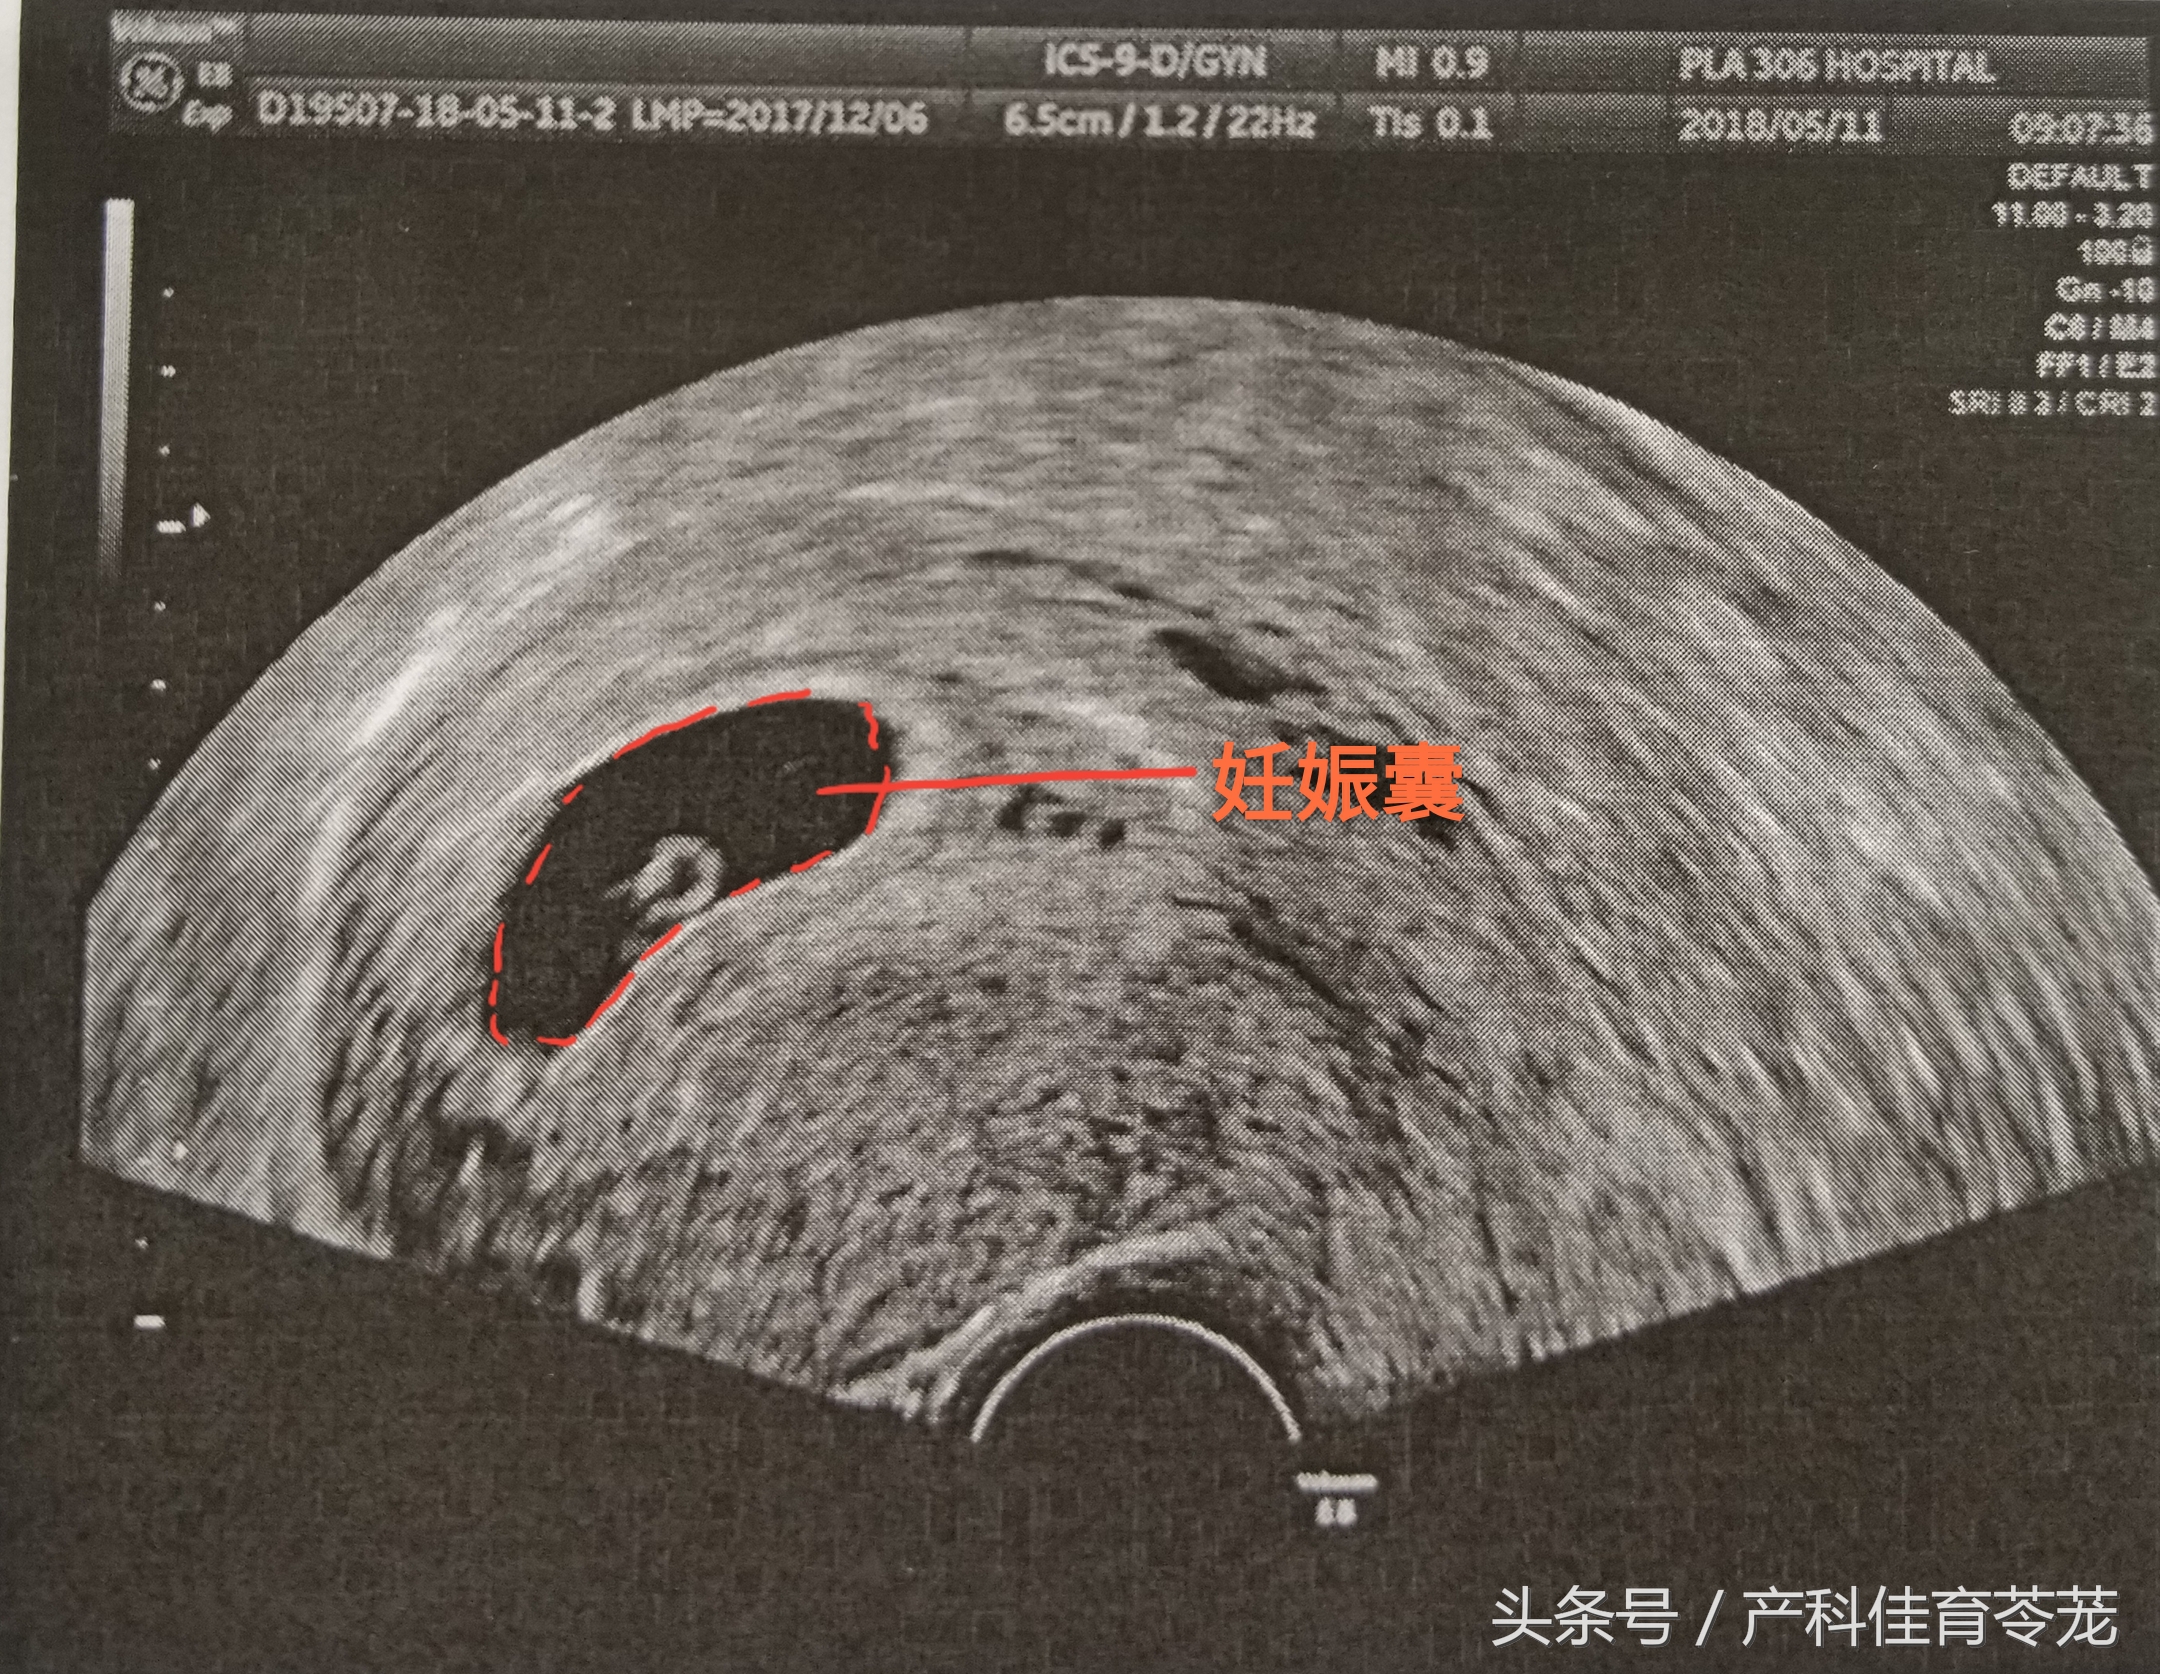

一、妊娠囊/胎囊(Gestational Sac GS)

b超的3组数字代表什么,b超图片上的数字

GS 是围绕胚胎的结构,是超声最先看到的妊娠结构

经腹超声(憋尿做的),在停经后5-6周可以看到,经阴道超声,在停经后4周就能看到。一般会测量GS的三个径线,所以您会看到“...X....X....cm/mm”的数值。

根据这些数值,可以用来确定妊娠时间:

妊娠天数=妊娠囊平均内径(mm)+30

妊娠周数=妊娠囊最大内径(cm)+3

注意:GS形态变异较大,根据它的测量值来推算孕龄的准确性较差